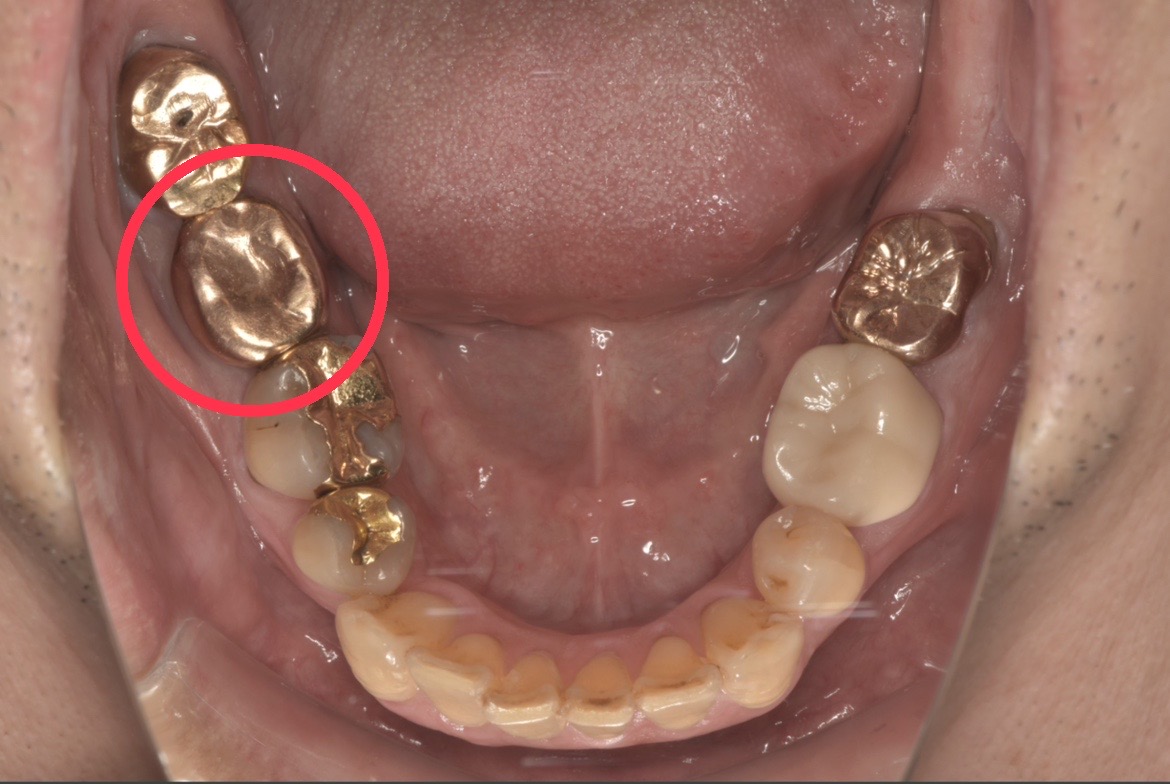

初診時の口腔内写真です。他院での根管治療の際にリーマーが折れ、歯の中に残ってしまっている症例です。